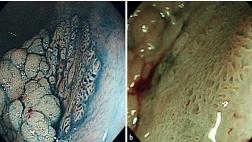

«Сегодня мы обладаем множеством уточняющих эндоскопических методов. Например, эндоскопическая ультрасонография, позволяющая оценивать структуру стенки исследуемого органа на оптическом срезе, а также оценивать параорганные структуры, лимфатические узлы. Также существуют методики, которые позволяют оценивать слизистые оболочки, отдельные клетки и даже их ядра. Соответственно, можно выставлять диагноз, не дожидаясь результатов биопсии. То есть непосредственно в процессе эндоскопического исследования.

Хочу сказать, что пациентам важно регулярно обследоваться. После 40 лет следует периодически делать гастроколоноскопию. В больницах, диагностических центрах врачи должны выявлять пациентов группы риска. А вот наши высокотехнологические методы мы применяем уже на пациентах группы риска. Например, если говорить про желудок, то это пациенты с хроническим атрофическим гастритом, кишечными метаплазиями. Для тонкого и толстого кишечника, это люди с полипами и другими заболеваниями кишечника. Разумеется, высокотехнологичные исследования нельзя поставить на поток и проверять всех подряд. Это просто неэффективно. Эти методы – для пациентов группы риска.

Задача онкологии – выявлять заболевание на самой ранней стадии. В некоторых локализациях даже удаётся обнаружить опухоль в нулевой стадии. С помощью эндоскопических методов мы можем выявить рак желудка, рак толстой кишки, рак лёгкого размерами несколько миллиметров и даже меньше. То есть это самая ранняя I стадия. Мы подвели статистику за последние 5 лет. В нашем центре рак желудка на I стадии удалось выявить в 28% случаев. Для сравнения, по стране этот показатель в три раза меньше.

В рамках национального проекта «Онкология», высокотехнологичные эндоскопические технологии должны применяться в каждом онкологическом центре страны. В каждую поликлинику такие приборы мы поставить не можем, но и нет такой задачи. Сегодня эндоскопия – это не только диагностика. Мы не только выявляем рак на ранней стадии, но и излечиваем пациента с помощью эндоскопической хирургии, удаляя опухоли даже достаточно больших размеров. Главное, чтобы не было глубокой инвазии. Наша задача – не только выявить, но и вылечить. И в последние годы это стало возможно».